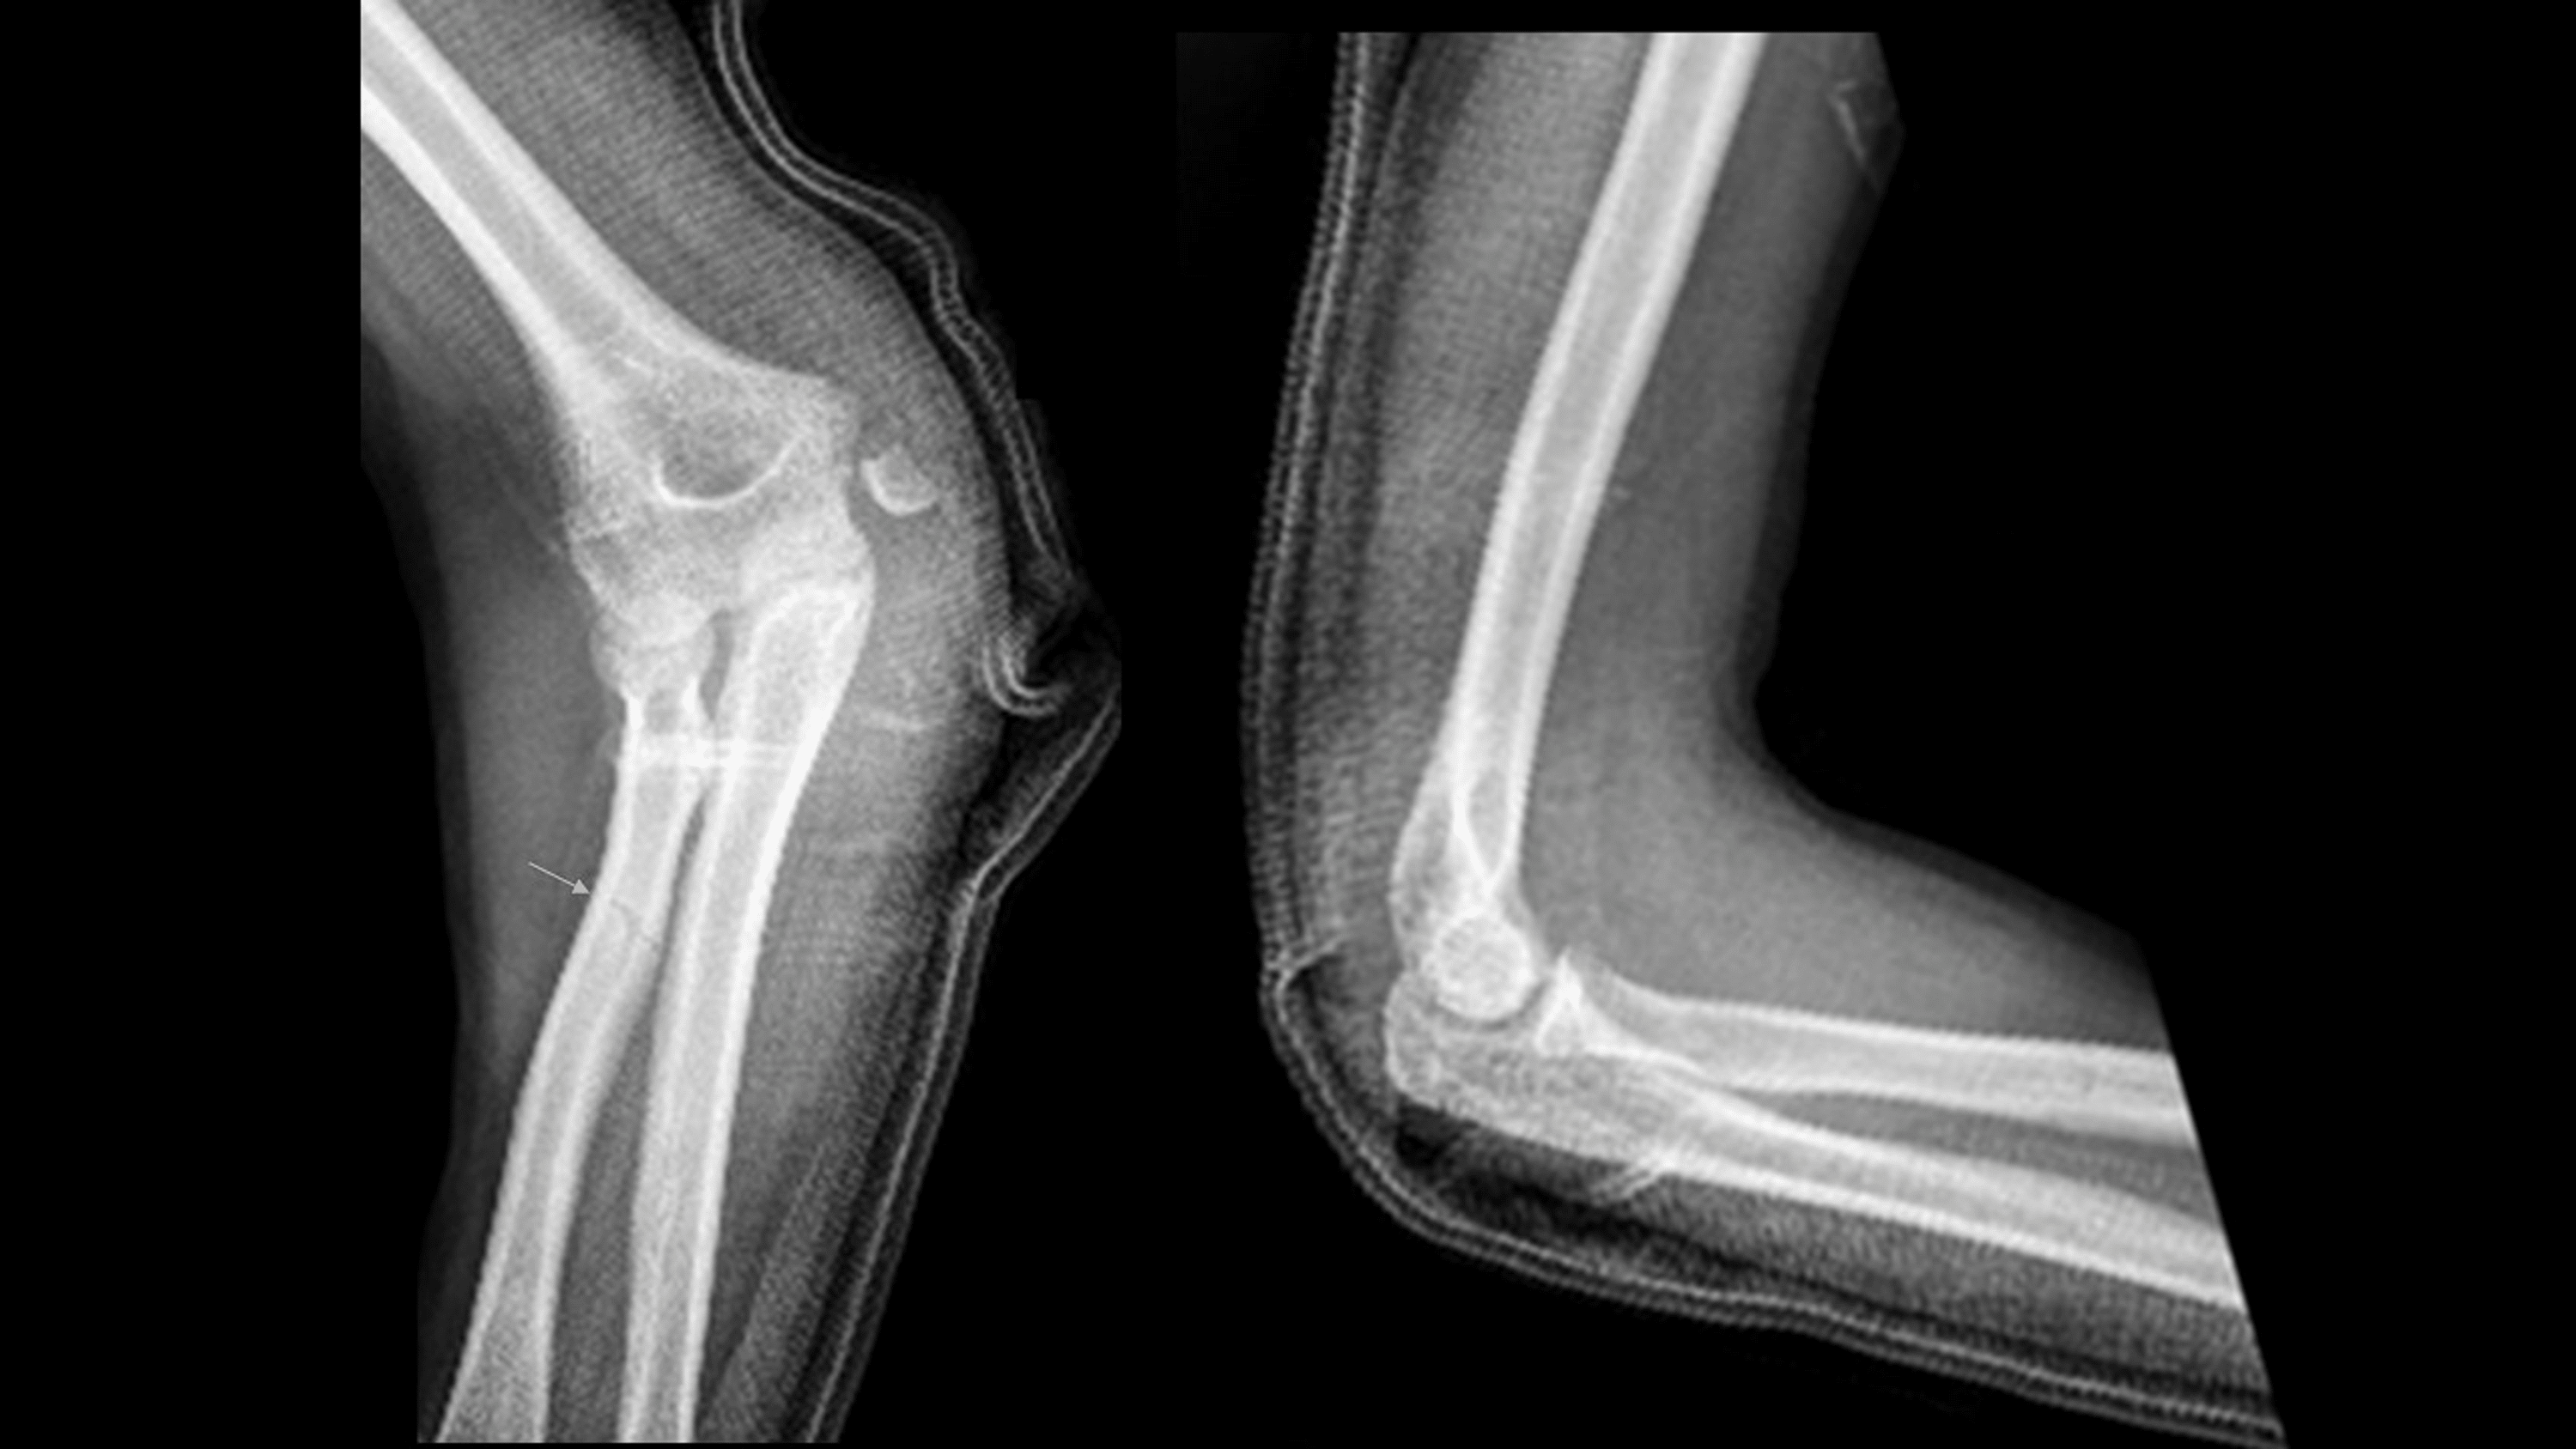

From radiopaedia.org

Posterior elbow dislocation Image Different Types Of Elbow Dislocation An elbow dislocation is defined as simple or complex *, the latter being. Elbow dislocations can be complete. Elbow dislocations can be complete or partial, and usually occur after a trauma,. Identify the typical patterns and common patient presentations with elbow dislocations. Elbow dislocations are common elbow injuries which can be characterized as simple or complex depending on associated. A. Different Types Of Elbow Dislocation.